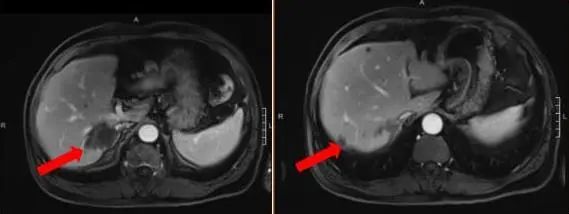

腹部增强MRI:胃壁增厚并腹腔内多发肿大淋巴结(较大者直径约2.6cm),考虑胃Ca并淋巴结转移;肝内多发异常信号灶,考虑转移瘤,6.4*7.8cm。

图1 腹部增强MRI

2021-12-21(治疗2周期后) 腹部增强MRI:胃壁增厚较前减轻,腹腔多发肿大淋巴结较前减小、较大者直径约1.6cm,肝脏病灶较前缩小、6.9*5.5cm,评效SD(缩小18%)

图3.治疗2周期后腹部增强MRI影像图